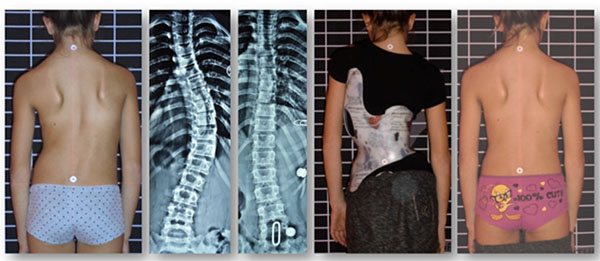

1. إذا كانت زاوية الانحناء متوسطة

عادة عندما تكون زاوية كوب بين 20 و40 درجة، يكون الحزام هو الخيار الأفضل لمنع زيادة الانحناء.

نجاح الحزام الطبي لعلاج اعوجاج العمود الفقري عند المراهقين لا يعتمد على ارتدائه فقط، بل على تفاصيل دقيقة مثل تصحيح الأنحناء وسرعة هذا التصحيح. متابعة الأهل مع الطبيب، الالتزام بعدد ساعات الارتداء، واستخدام الحزام المصمم خصيصًا لكل طفل، جميعها عوامل تزيد من فعالية العلاج وتمنح الطفل فرصة أفضل لنمو ظهر مستقيم وحياة طبيعية.

التطور الكبير في تصميم الأحزمة الطبية جعل علاج اعوجاج العمود الفقري عند المراهقين أكثر نجاحًا وأقل إزعاجًا. باستخدام تقنيات التصوير الثلاثي الأبعاد والمحاكاة الرقمية، أصبح الحزام أكثر خفة وراحة، ويعطي نتائج أفضل في تصحيح الانحناء والتواء العمود الفقري.